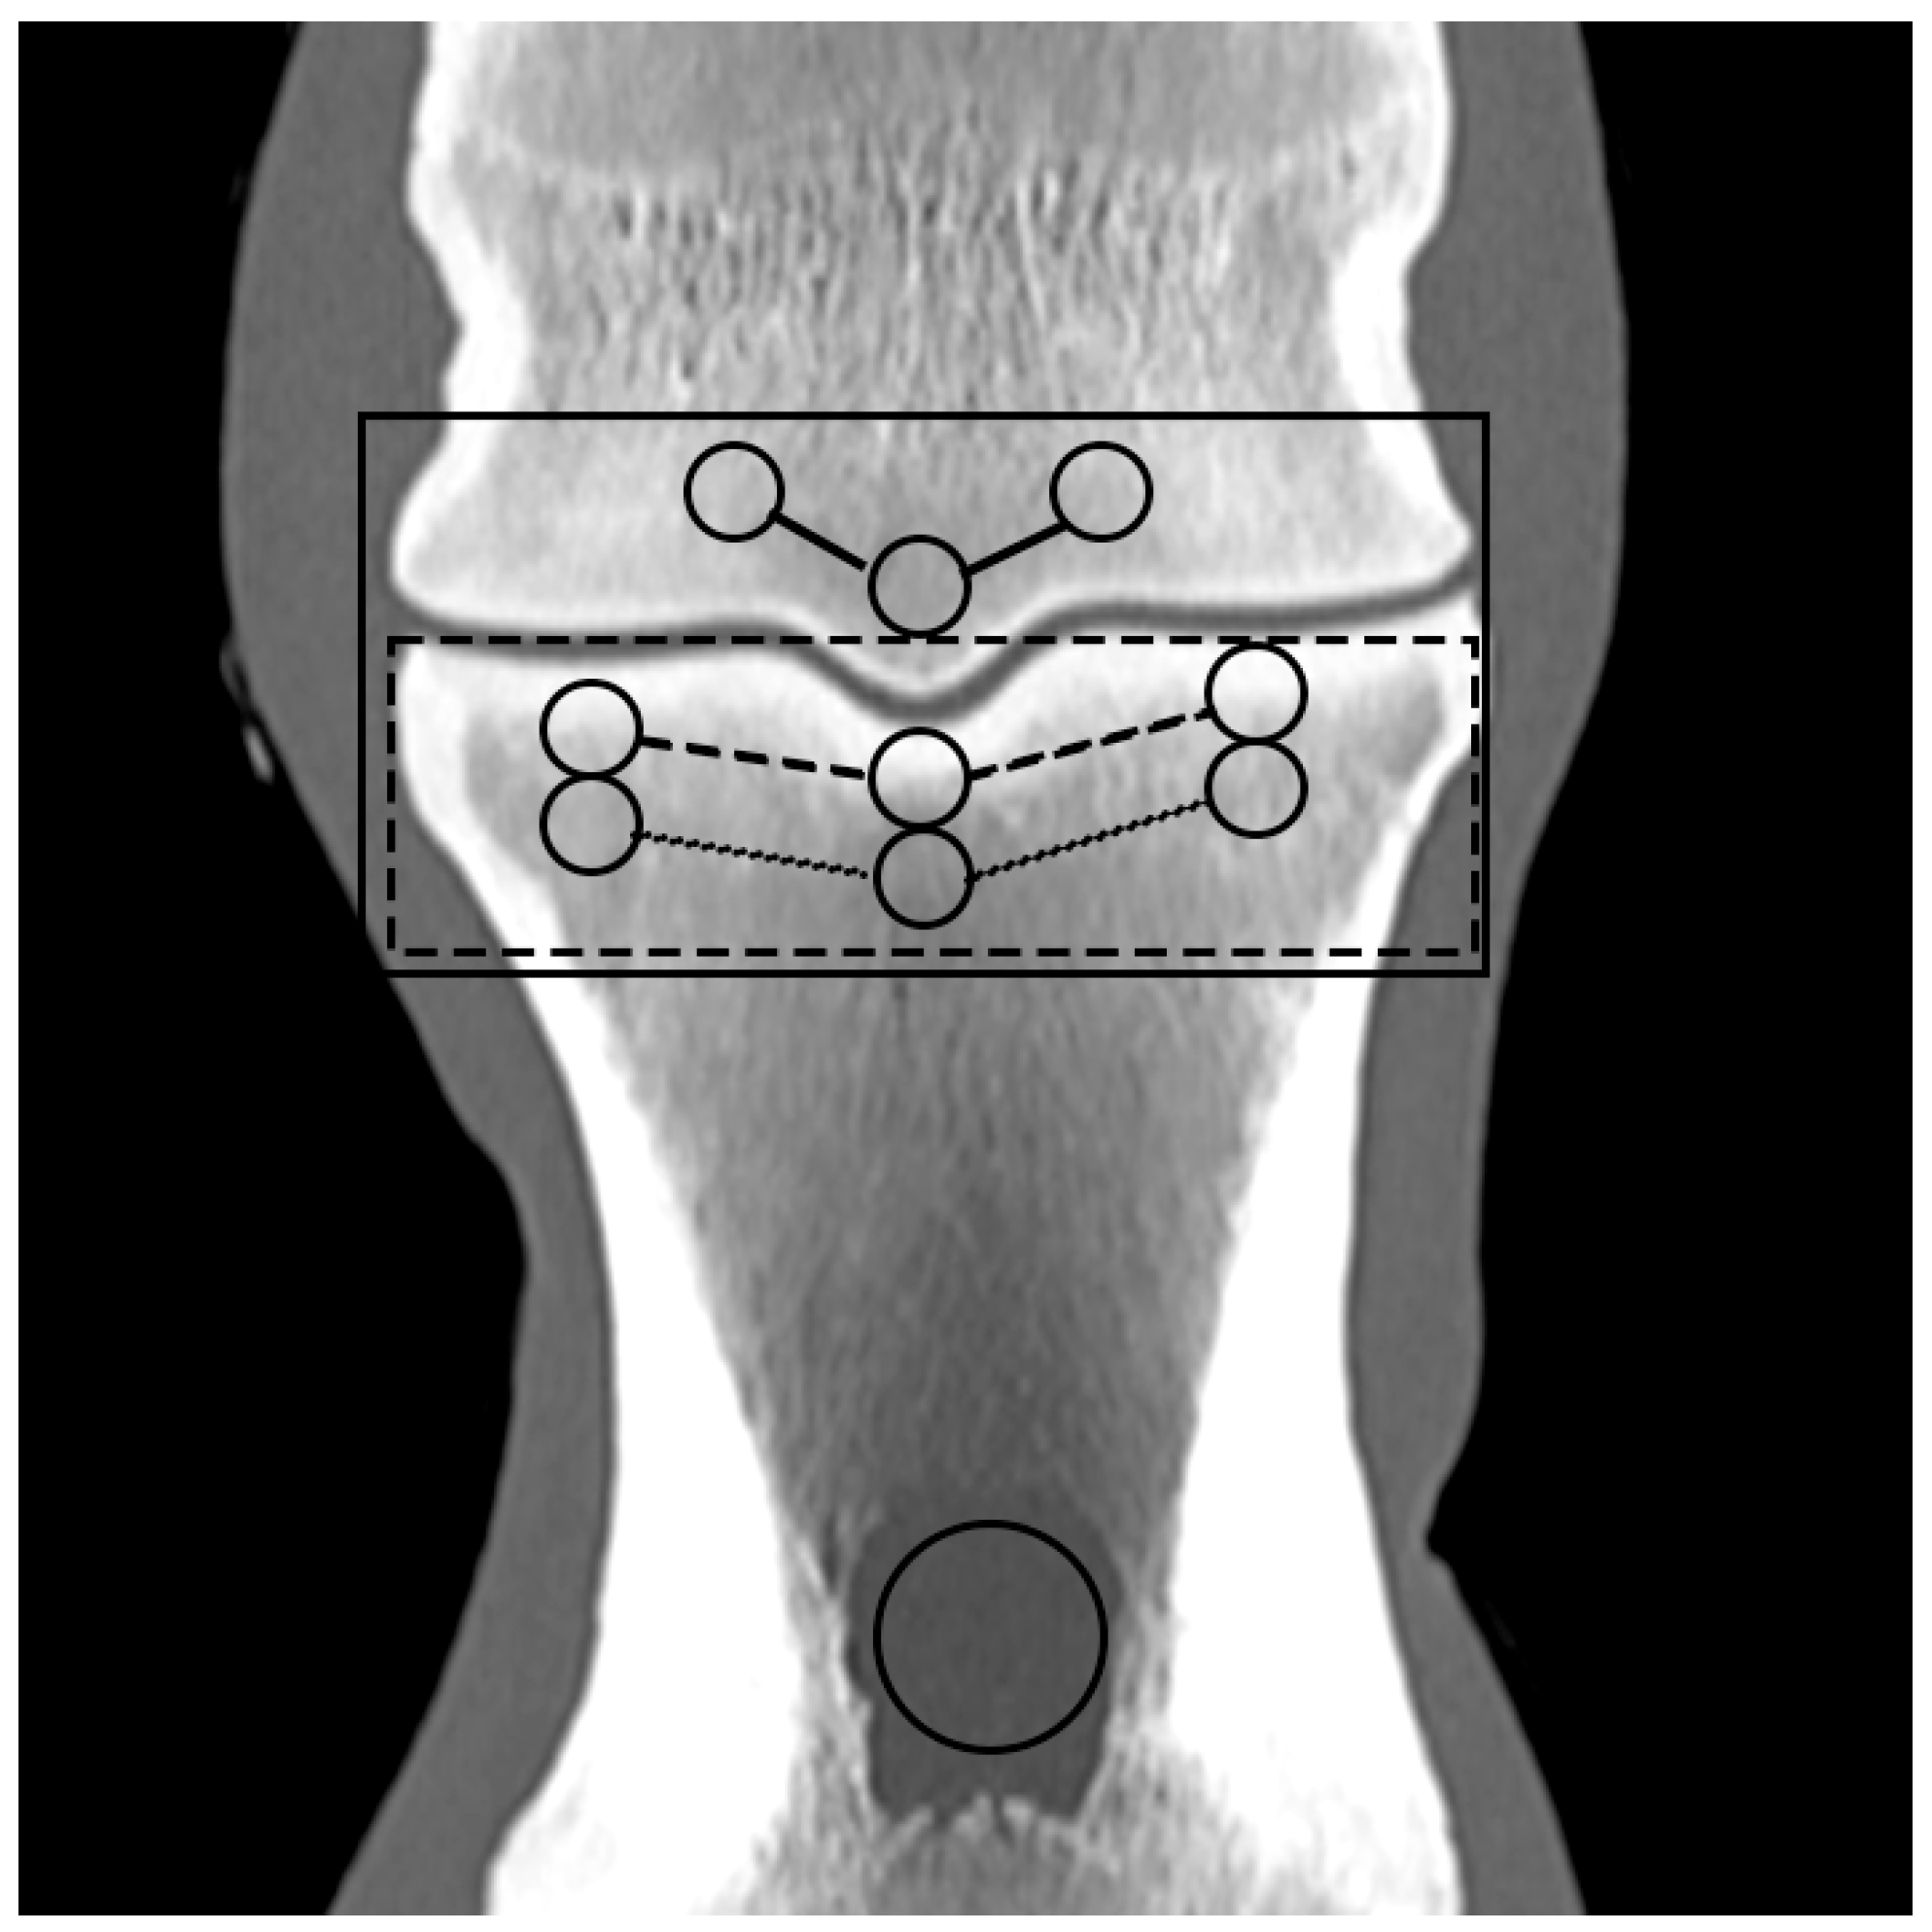

Based on the CT raw data, EAN and ED maps were created from both SSDECT and SBCT images (slice thickness 2 mm), and ROIs were drawn in the virtual monochromatic images (window level 500, window width 2500) using the proprietary software (Raw Data Analysis, CANON Medical and Intellispace Portal 12, Philips Healthcare). Mean EAN/ED values were recorded for each ROI. In total, 29 ROIs and 16 zones were defined for each distal limb. A zone referred to a certain anatomical area, and the mean EAN/ED was calculated from all ROIs included in this area. In the distal aspect of the third metacarpal (MC) and metatarsal (MT) bone, a mid-dorsal image was chosen, and one ROI each was placed in the subchondral bone of the sagittal ridge and the medial and lateral condyle, respectively (dorsal MC/MT zone) (Figure 1). Additionally, a transverse image was chosen at the level of the maximum width of the proximal sesamoid bones (PSB), i.e., at the transition from the distal to the mid-third of the PSBs, and 1 ROI each was placed in the palmar/plantar subchondral bone of the medial and lateral metacarpal/metatarsal condyle (plantar MC/MT zone) and the dorsal subchondral bone of the medial and lateral proximal sesamoid bone (PSB zone) (Figure 2). The mean of all palmar/plantar ROIs in the FJ area (plantar MC/MT and PSB ROIs) represented the palmar/plantar FJ zone (Figure 2). In the first (P1) and second (P2) phalanx, a mid-dorsal image was chosen at the level of the marrow cavity or nutrient foramen, respectively, and in the third phalanx (P3), a dorsal image was chosen parallel to the dorsal surface of the bone at the level of the solar canal. Three ROIs each (medial and lateral fovea, sagittal groove or extensor process) were drawn in the proximal subchondral bone (proximal P1/P2/P3 subchondral zone) and trabecular bone (proximal P1/P2/P3 trabecular zone) distal to the latter in all phalanges (Figure 1 and Figure 3). Larger zones were calculated including all ROIs in the proximal subchondral and trabecular bone of P1, P2 and P3, respectively (proximal epiphyseal P1/P2/P3 zone) (Figure 1 and Figure 3). Moreover, the mean of all dorsal ROIs in the FJ area (distal MC/MT, proximal P1) represented the dorsal FJ zone (Figure 1). A single ROI was also applied to the marrow cavity of P1 (Figure 1). On a mid-dorsal plane of the NB, 3 ROIs were evenly distributed medially, centrally, and laterally within the spongious bone (navicular zone) (Figure 4). All ROIs were of a circular shape with a diameter of 4 mm (smallest ROI possible for both CT units) except for the circular ROI in the marrow cavity of P1, the diameter of which was adapted to the size of the marrow cavity.

Figure 1. Regions of interest (ROIs; circles) and zones (mean EAN calculated from all ROIs included in an anatomical area; lines) in the dorsal aspect of a front fetlock joint on a mid-dorsal monoenergetic image (detector-based spectral computed tomography, Philips): ROIs in the medial and lateral metacarpal/metatarsal condyle (dorsal MC/MT zone; continuous line), the proximal subchondral and trabecular bone of the proximal phalanx (proximal P1 subchondral/trabecular zone; dashed/dotted line), the marrow cavity of P1, and the proximal epiphyseal P1 zone (dotted rectangular line) and dorsal FJ zone (continuous rectangular line).